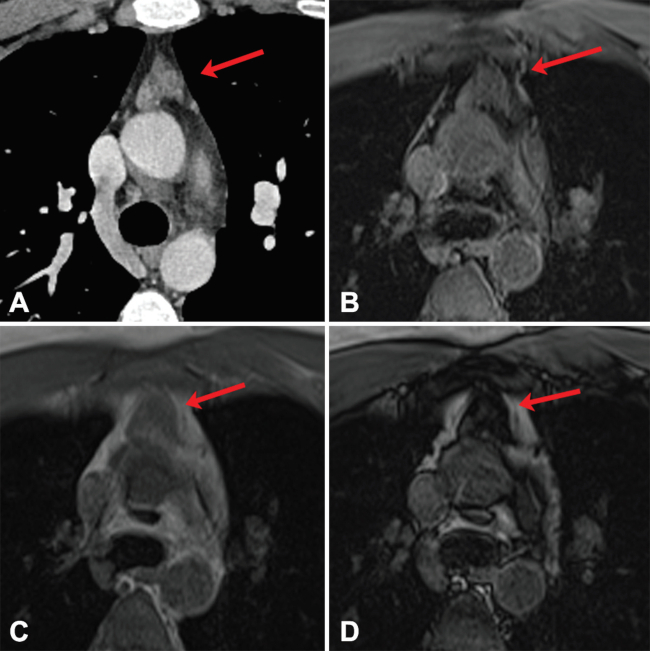

En timomas, la imagen en TC generalmente evidencia una masa homogénea de partes blandas con bordes bien delimitados y una morfología lobulada, redonda u ovalada. En ocasiones, se pueden ver calcificaciones o componentes de baja densidad que representan necrosis (especialmente en tumores grandes) (►Fig. 5).16 Hasta el 5% de los timomas invasivos pueden tener metástasis al momento de presentación y el PET-CT, siendo un método de evaluación de todo el cuerpo, es de utilidad para detectarlas.17